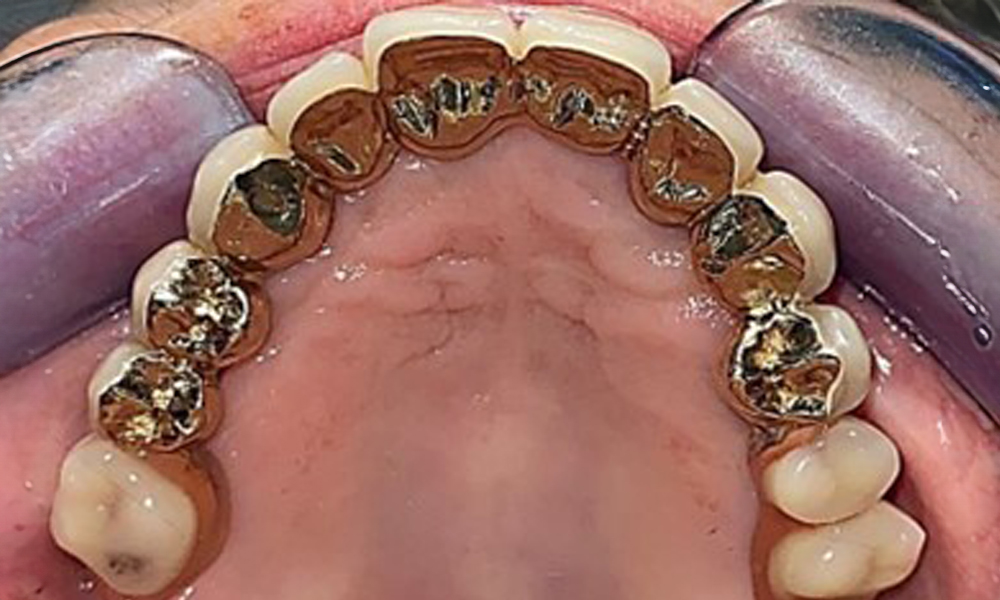

Der dentale Befund stellt sich wie folgt dar: Kombinierte herausnehmbare Implantat- und zahngetragene Teleskoparbeit auf Implantaten 15, 13, 21, 23, 24, 25 und Zahn 11 (Abb. 1, Abb. 2, Abb. 3). Im Unterkiefer ist die Patientin mit einem festsitzenden Zahnersatz versorgt. 37–34 sowie 45–47 haben suffiziente Brücken (Abb. 4). Kronenränder sind intakt, aktive kariöse Läsionen sind nicht vorhanden. An Zahn 43 zeigt sich eine Compositefüllung mit Randspalt. Im Unterkiefer liegen Rezessionen mit freiliegender Wurzeloberfläche zwischen 1 – 3 mm vor. Dies trifft auch für 11 zu.

Okklusalansicht Unterkiefer

Abb. 4: Okklusalansicht Unterkiefer